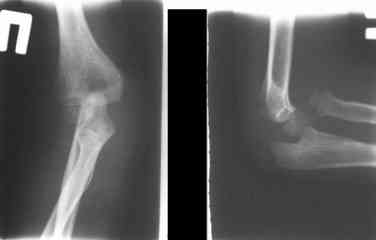

Иллюстрация к лечению застарелого повреждения Монтеджиа

Пациентка клиники детской травматологии ЦИТО

Уважаемые коллеги, кто-нибудь еще видит здесь застарелое повреждение Монтеджи? Может мне показалось?

Колеги!!! Сконцентрируйтесь... Не спешите и подумайте, что препятствует головке луча вернуться на свое место??? Отвыкание :):):) Конечно нет. Внимательно посмотрите на ось локтевой кости. Как раз она мешает вернуться лучу на место. Зря Монтеджи старался, что ли???

Многоуважаемые коллеги, всем большое спасибо!!! Да, здесь было повреждение Монтеджиа, когда нарисовал скиаграмму все стало понятно. Мне очень понравились рекомендации Константина Требухина, только немножко видоизменил; я считал так, если деформацию исправить то локт/кость должна удлиниться, и во вторых, если на аппарате низвести лучевую кость, то может наступить позиционное несоответствие в дистальном радиоульнарном сочленении. 28.02.08г операция - шарнирная остеотомия локтевой кости на уровне деформации, далее вскрыт плечелучевой сустав, удалены рубцовые тканы, после исправления варусной деформации и создания физиологического изгиба локтевой кости головка луча легко вправился, из части рубцовой ткани сделана пластика кольцевндной связки, трансартикулярная фиксация спицей, локтевая кость двумя спицами.